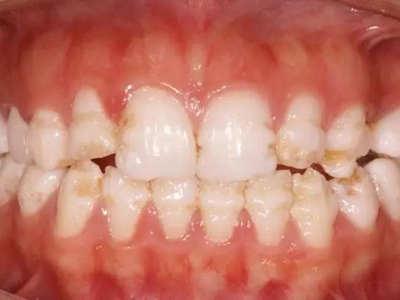

牙釉质发育不全牙齿表面棕色有坑图

牙釉质发育不全导致牙釉质表面呈棕褐色,有带状、窝沟状凹陷,以及黑点,牙釉质大面积缺损,牙齿表面变得粗糙,可出现进食时敏感等不适。